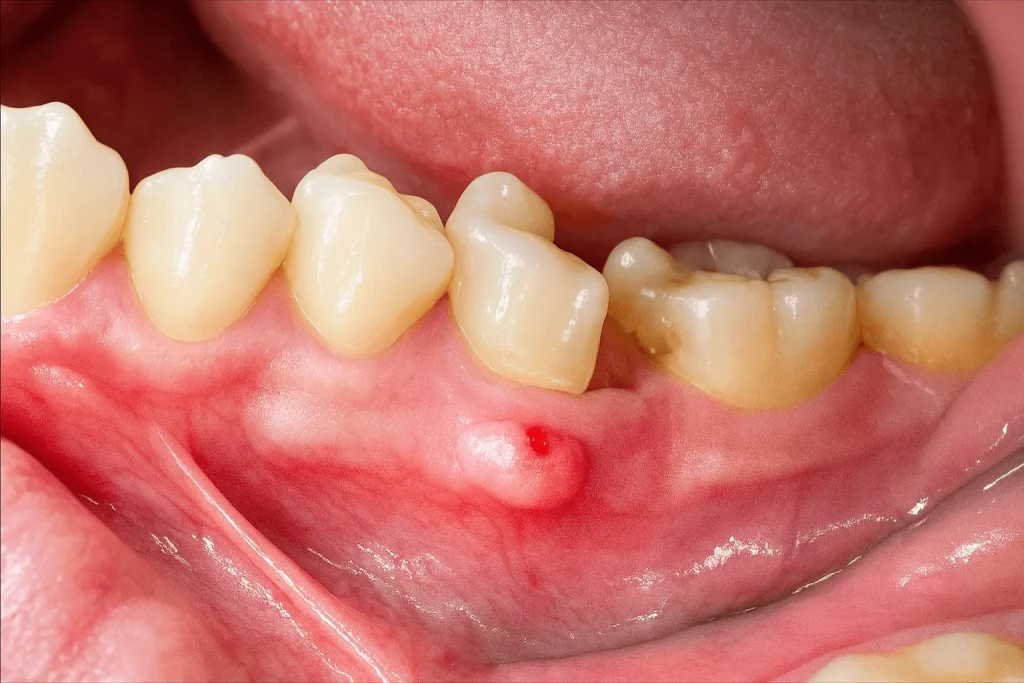

یکی از دغدغههای کاشت ایمپلنت، آبسه لثه بعد از ایمپلنت است. دلیلی که آبسه لثه بعد از جراحی و کاشت ایمپلنت به عنوان یک دغدغه محسوب میشود، این است که آبسه امکان تورم، التهاب و عفونت در ایمپلنت را بالا میبرد!

این موضوع میتواند برای سلامت دهان و دندان به عنوان یک خطر جدی به حساب بیاید و دوام ایمپلنت را کم کند و موجب شکست آن شود. علائمی مانند درد، چشم و بوی بد دهان از مهمترین نشانههای آبسه به شمار میآیند. اما گفتنی است که آبسه لثه بعد از کاشت ایمپلنت، قابل درمان است. تنها نکته مهم این است که آبسه و دلیل به وجود آمدنش را بشناسیم تا بتوانیم بهترین راهکار را برای برطرف کردن آن در نظر بگیریم.

عفونت را نباید با آبسه اشتباه گرفت! در واقع آبسه ایمپلنت، نشانه شروع عفونت در آن ناحیه است. به همین خاطر، آبسه بعد از ایمپلنت را باید جدی گرفت. برای اینکه بتوان عفونت را از آبسه تشخیص داد، بهتر است نشانههای هر کدام را بررسی کرد. آبسه معمولا با چرک و تورم نقطهای و درد همراه است اما عفونت با التهاب و تحلیل استخوان در اطراف ایمپلنت، خود را نشان میدهد.

علائم آبسه چرکی و شدید

- مشاهده واضح چرک و احساس درد شدید: این دو علامت را نباید دستکم گرفت و بهتر است هر چه سریعتر به پزشک مراجعه کرد.

- درد با احساس ضربان: زمانی که درد با حالت کوبشی مانند ضربان همراه است، احتمال چرک، بسیار زیاد است.